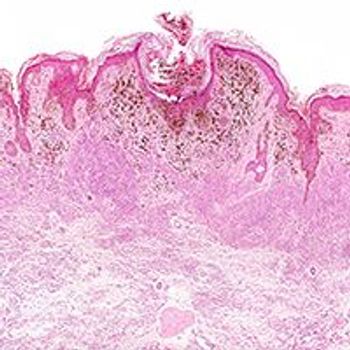

The Melanoma Institute Australia nomogram was found to accurately estimate the risk of sentinel node metastasis positivity in patients with melanoma and its use could help to reduce the rate of unnecessary invasive biopsies without sacrificing sensitivity.